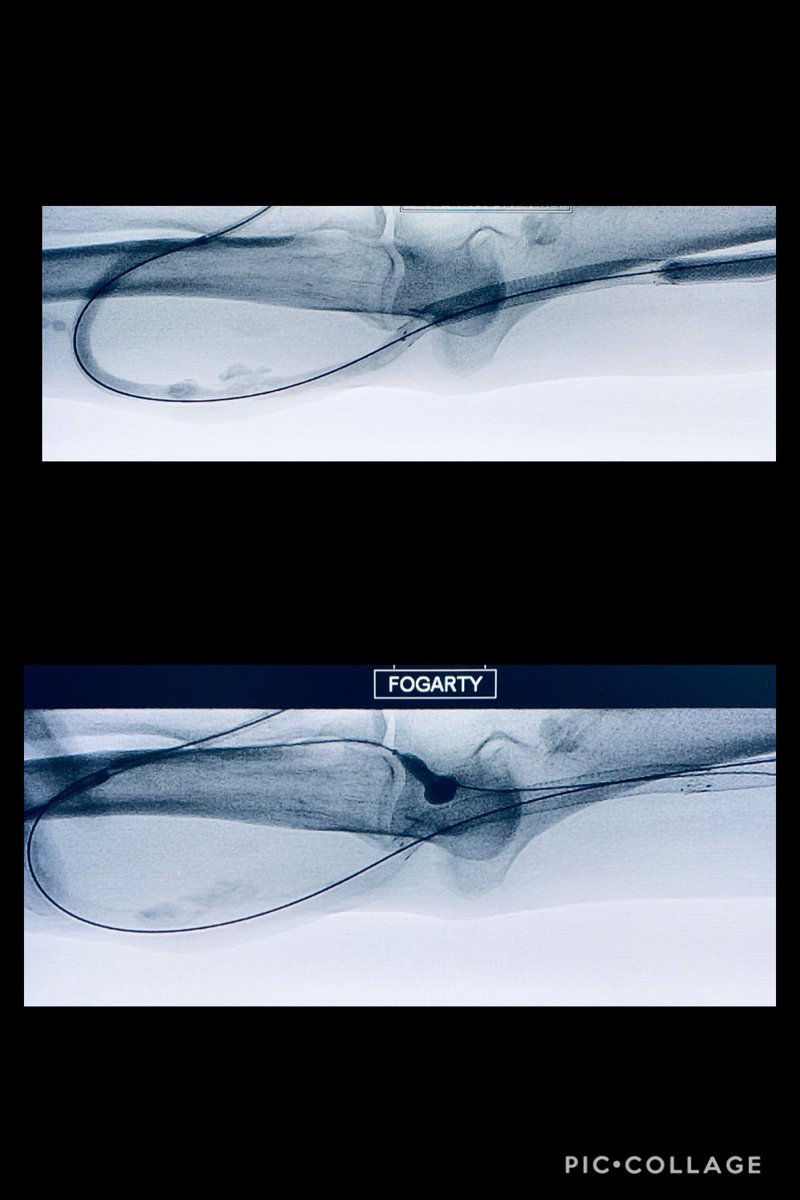

Patient with significant lower extremity swelling with #IVC thrombosis post single session mechanical thrombectomy using Lighting Flash, symptoms improved within 24 hrs #irad #SIR #IRadRes #futureradres @SIRspecialists @SIRRFS @columbiaimaging @columbiaradres @noorahmadmd